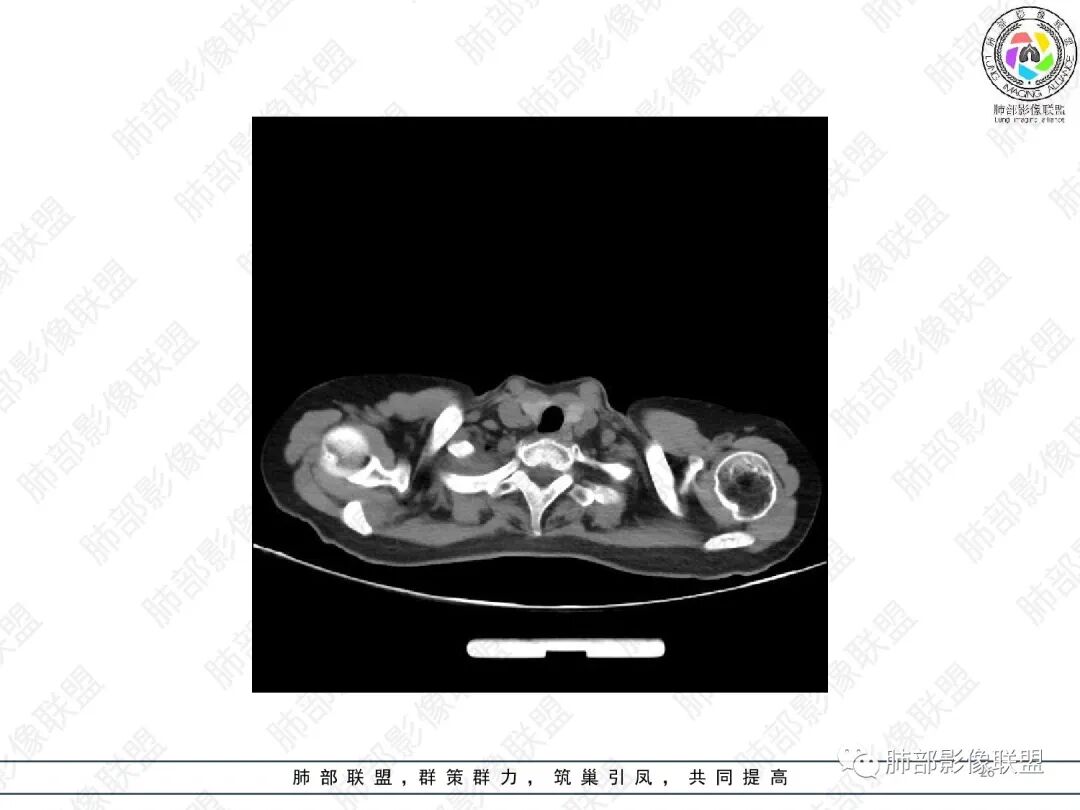

2.胸部CT:右肺上叶及中叶不规则块状影,沿支气管走行方向指套样影,支气阻塞湖嵌塞,腔内可见高密度影。灶周可见磨玻璃,外围见结节影及树芽征。左肺体积缩小,见不规则条索影、胸膜增厚,纵隔牵拉左移。

3.综合分析:结合患者病史及胸部CT主要鉴别ABPA(右肺上叶不规则块影,指套样顺延支气管方向,抗结核治疗1年,肺部病灶仍明显)及继发性肺结核TB(右肺上叶不规则肿块,其可见高密影,边缘模糊,周围卫星灶、树芽征,沿支气管爬行)。

完善气管镜及病理、检验结果(IgE显著增高)等支持ABPA诊断。且给予激素及伊曲康唑治疗后复查胸部CT提示病灶较前吸收,所以诊断明确。